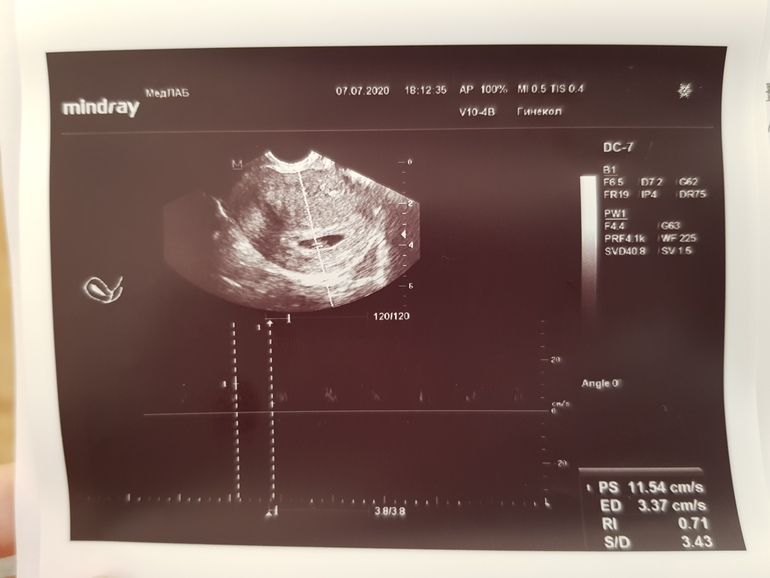

Подскажите, пожалуйста, у меня есть снимок с узи, как я понимаю где идёт измерение ЧСС( а может и нет, ничего в УЗИ не понимаю)

Так вот, в заключении УЗИ стоит ЧСС 110, переживаю что это очень мало, срок был 6.4 по УЗИ. Но у врача в заключении было несколько опечаток, по ктр в том числе. Я все надеюсь, что может и с ЧСС ошиблась.

Посмотрите, пожалуйста, может быть вы что-нибудь увидите. Потому что 110 я нигде не вижу на фото

Мой снимок с чсс в 6,2 недели выглядил так...